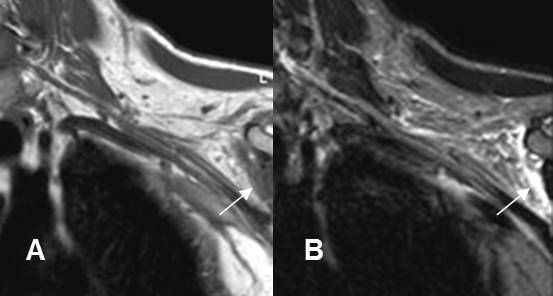

A: RM coronal en T1y B: RM coronal en STIR. Cambios inflamatorios por encima de los vasos subclavios, que rodean las raíces nerviosas, las cuales permanecen integras. La lesión se produjo después de una luxación de hombro.